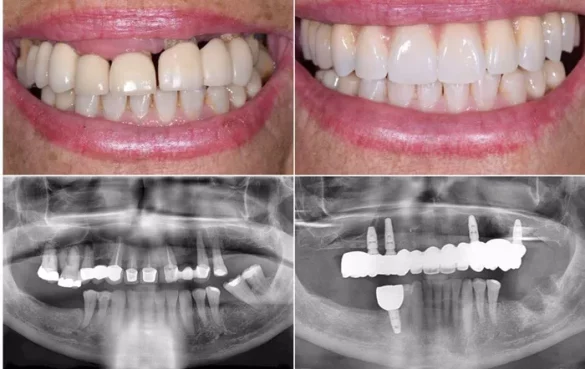

All-On-4 dental implants are designed to restore a full arch of teeth using four implants placed in the jawbone. These implants act as artificial roots and support a custom-made bridge of replacement teeth. Unlike dentures, the prosthetic teeth remain fixed in place and do not require adhesives or removal.

The treatment is typically considered for patients who have lost most or all teeth in one arch, or whose remaining teeth cannot be restored effectively. By anchoring a full set of teeth to implants, the approach aims to improve stability and restore normal oral function.